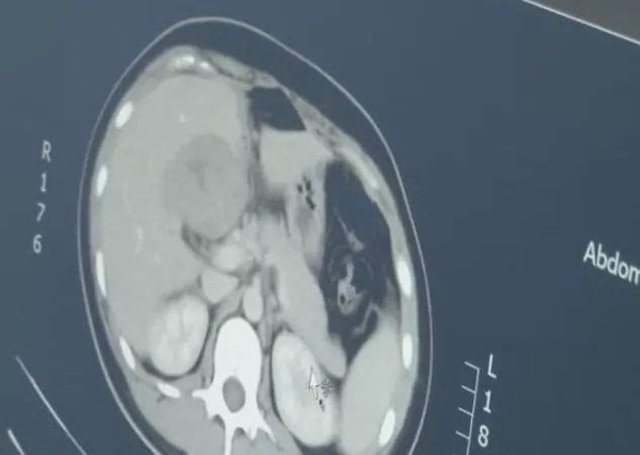

نەچچە كۈن ئىلگىرى، ئەنخۇي ئۆلكىسىدىكى يۇۋ خانىم قوسىقى بىئارام بولغانلىق سەۋەبىدىن، ياڭجۇ شەھىرىدىكى بىر دوختۇرخانىغا بېرىپ تەكشۈرۈش قىلدۇرغان؛ بىراق ئويلىمىغان يەردىن، دوختۇرلار يۇۋ خانىمنىڭ جىگەر قىسمىدا بۆرتۈپ چىققان بىر قاپ بايقىغان بولۇپ، بۇ قاپسىمان جىسىم ئەسلىدە بىر تۆرەلمە ئىكەن.

دوختۇرنىڭ تۇنۇشتۇرىشىچە، يۇۋ خانىم بۇيىل 29ياشقا كىرگەن بولۇپ، تەكشۈرۈش داۋامىدا ئۇنىڭدا ھامىلدار بولغانلىق ئالامەتلىرى بايقالغان، ئەمما ئۇنىڭ بالىياتقۇسىدا ھامىلدارلىق خالتىسى بايقالمىغان.

بۇ ۋاقىتتا دوختۇرلار، يۇۋ خانىمنى بالىياتقۇ سىرتىدا ھامىلدار بولۇپ قالغان ئوخشايدۇ دەپ گۇمانلانغان؛ ئەمما CT تەكشۈرۈش نەتىجىسىدە بايقىلىشىچە، تۆرەلمە جىگەرگە بېرىپ قالغان. بۇ ئەھۋال، ئىنتايىن ئاز كۆرىلىدىغان بىر خىل بالىياتقۇ سىرتىدا ھامىلدار بولۇش بولۇپ، ئاسانلا چوڭ قان كىتىشنى كەلتۈرۈپ چىقىرىپ، ئانا-بالىنىڭ ھاياتىغا خەۋپ ئېلىپ كىلىدىكەن.